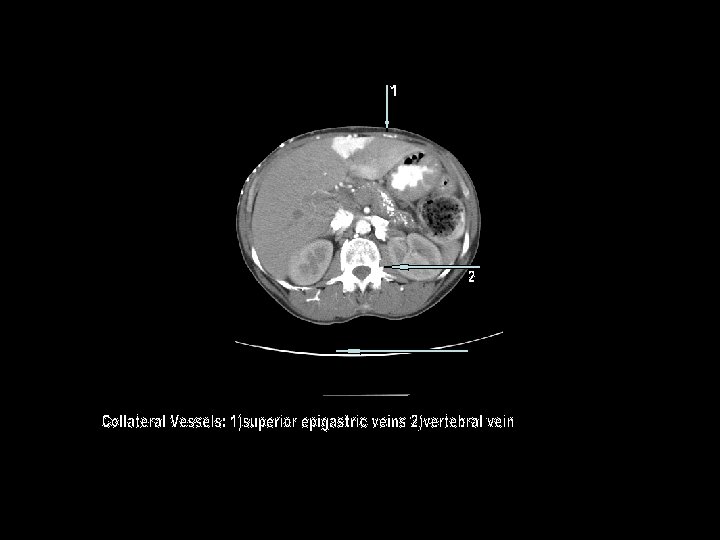

Venous Collaterals 1

Venous Collaterals Recruited to Bypass SVC and Azygous Veins 1 1

This case represents a Type 4 SVC obstruction, and demonstrates the collateral venous anatomy when the SVC is obstructed below the level of azygous insertion. With a patent azygous vein and the obstruction above the level of the azygous, collateral flow can travel retrograde into the left brachiocephalic vein to accessory hemiazygous vein to azygous vein and then flow antegrade through the distal SVC. With the Type 4 obstruction the collateral circulation is routed to the inferior vena cava or portal circulation by multiple venous plexuses, including: thoracoepigastric vein, mediastinal vein, internal mammary vein, hemiazygous vein, lateral thoracic vein, pericardiophrenic vein, paravertebral vein, intercostal vein, capsular /surface liver vein, bilateral phrenic veins, thoracodorsal scapular vein, superior/inferior epigastric vein, accessory hemiazygous vein. Another intriguing pathway illustrated in this example is the cavo-portal pathway associated with intense opacificaton of the quadrate lobe– a sign with high specificity for SVC obstruction. It is associated with communication of the internal mammary veins with the epigastric veins, which then anastomoses with the peri-umbilical venous channels. Through the recanalized umbilical vein in the falciform ligament, blood flows retrogradely into the left portal vein. The resultant flow and venous stasis is believed to result in the characteristic focal hepatic enhancement. Similar findings are observed nuclear imaging with Tc-99 m sulfur colloid scans, the so-call focal hepatic hot spot sign.